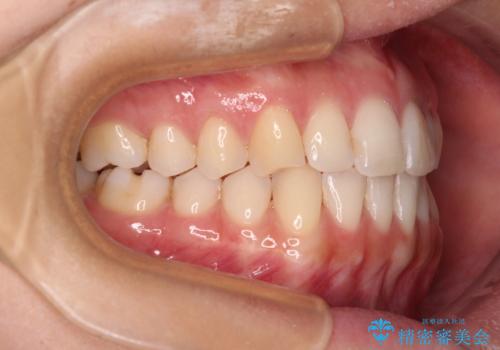

前歯の重なりをインビザライン・モデレートで矯正治療

- 上下前歯の重なりを気にして来院された患者様です。

安価なインビザラインパッケージを用いての治療を希望されており、デコボコの程度が中等度であったため、インビザライン・モデレートを用いて矯正治療を行うこととしました。